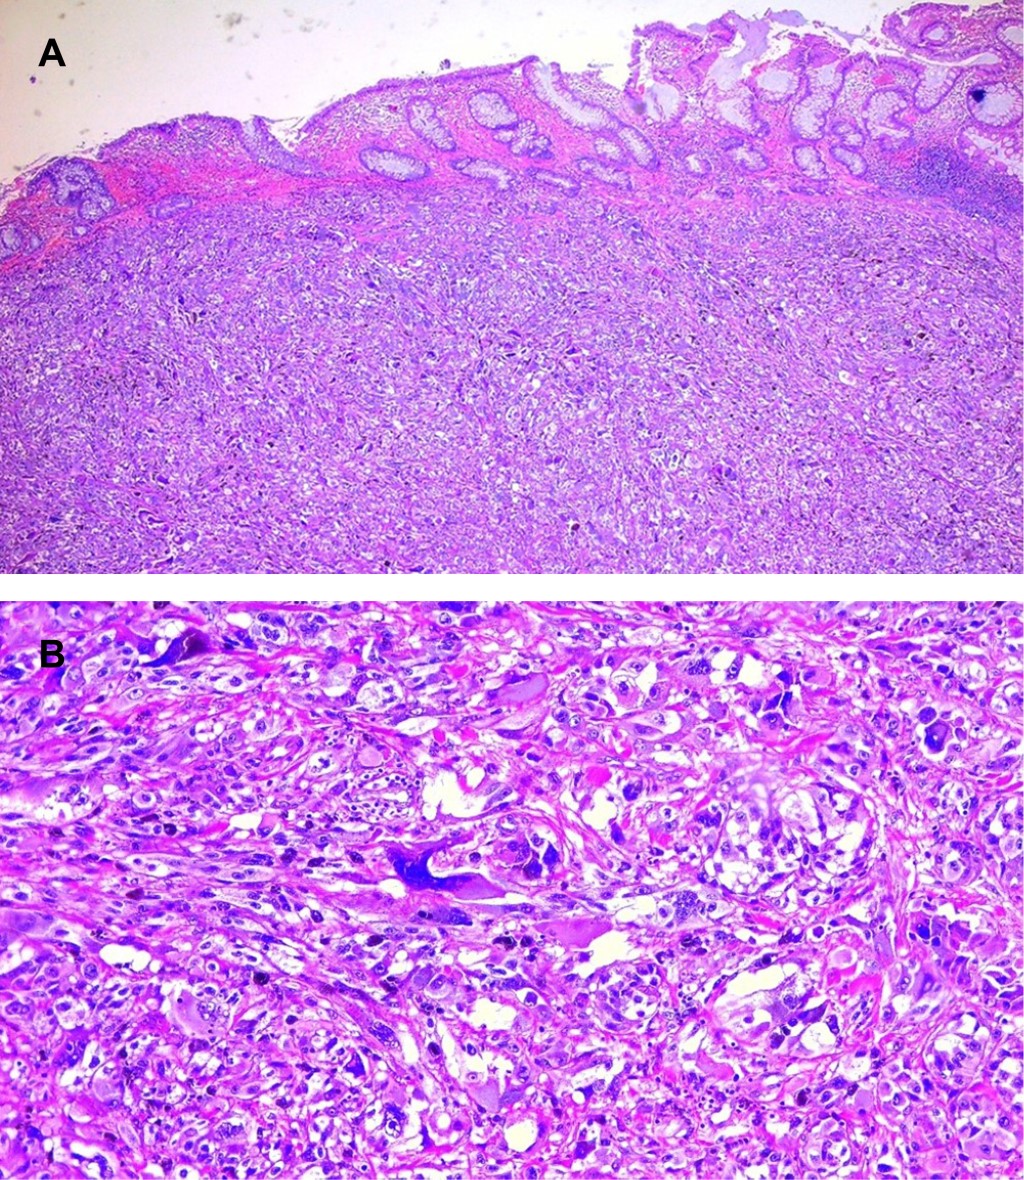

Anorectal melanoma is rare, with 0.4 to 1.6% of all melanomas and 0.5% of anorectal malignancies. Frequently confused with hemorrhoidal disease and polyps. A 53-year-old female with no previous history presented with a foreign body sensation in the anal region and rectorrhagia of two months' evolution. On proctologic examination, an indurated mass was detected in the left lateral region, 4 cm from the anal margin, and an examining glove came out with hematic debris. Colonoscopy reports a 2 cm pedunculated, friable, pigmented lesion located laterally in the dentate line. He underwent a wide local transanal resection (WLTR). Pathology reports malignant melanoma, positive resection margins, and in contact with neoplastic cells. She is subsequently treated with Nivolumab and adjuvant radiotherapy. The surgical options are WLTR and abdominoperineal resection (APR). Traditionally APR was considered the best option for locoregional control of the disease. However, recent studies report no difference in survival compared to WLTR. Most patients are diagnosed late in the disease; therefore, curative surgery is impossible.

Figure 1